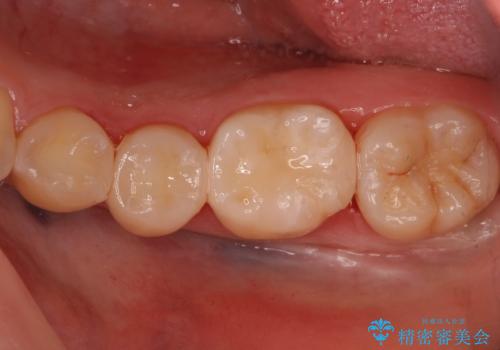

歯と歯の間の虫歯 セラミックインレーでの治療

歯と歯の間に虫歯があったため適合の良いセラミックインレーで修復処置をしていきました。

- 左下567 セラミックインレー 77,000円×3本費用は治療当時の料金となります